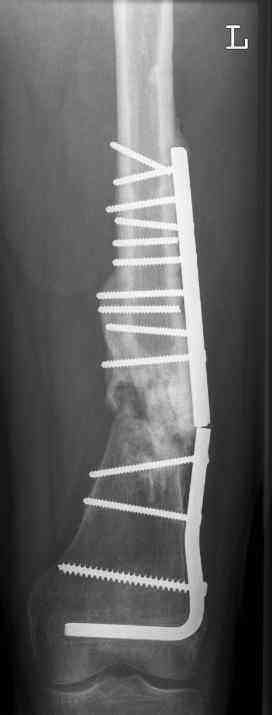

aug 06: blade plate + bone graft

nov 06: revision blade plate

feb 07: retrograde nail + bone graft + BMP

may 07: dynamisation nail

sept 07: locking screw removal (max. dynamisation reached)

nov 07: persistant non-union distal femur; other fractures healed uneventfully.

All with gradual/partial weightbearing etc. Currently 50-100% weight bearing, no pain.

Soft tissues are intact. No smoking or diabetes.CRP <2